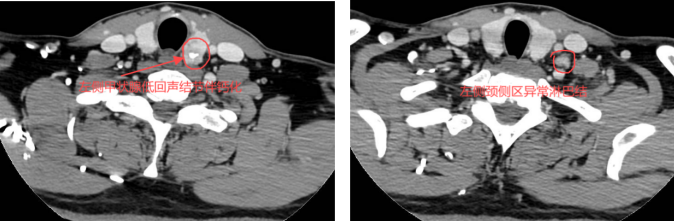

经检查,丁先生左侧甲状腺低回声结节-4b级,且合并左侧颈侧区淋巴结异常。为进一步诊治入住我院甲状腺外科,经过全面检查评估后诊断:1、左侧甲状腺结节——恶变可能?2、左侧颈侧区淋巴结异常-转移可能?术前增强CT提示:左侧甲状腺低回声结节伴钙化及左侧颈侧区异常肿大淋巴结。

术前增强CT提示:左侧甲状腺低回声结节伴钙化及左侧颈侧区异常肿大淋巴结